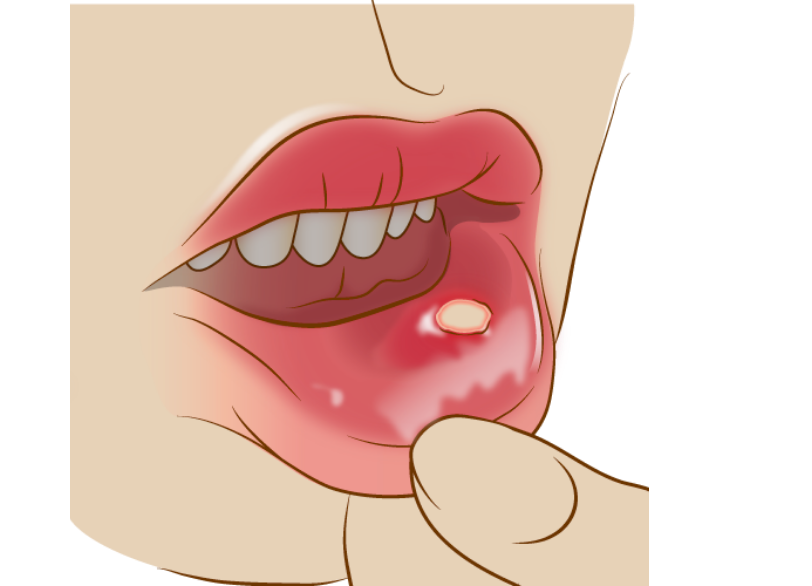

その他のお口のトラブル

粘膜疾患・外傷・感染症

お口の中には歯や歯ぐき以外にも、舌、頬の粘膜、唇、唾液腺など様々な組織があります。

これらの異常に対しても、専門的な診断と治療を行います。

口内炎・粘膜の異常

「口内炎がなかなか治らない」「舌に白いできものができた」「頬の粘膜が赤い」

一般的な口内炎であれば、塗り薬やレーザー治療で早期に治癒します。

当院の「Fotona社製ライトウォーカー(歯科用レーザー)」を照射することで、殺菌・消炎効果を高め、痛みを即座に和らげることができます。

しかし、中には「口腔がん」の前癌病変(がんになる手前の状態)や、初期の口腔がんである可能性もゼロではありません。

2週間以上治らない口内炎や、しこりのあるできものは要注意です。

当院では視診・触診による一次スクリーニングを行い、悪性の疑いがある場合は、速やかに専門機関へ紹介する連携体制をとっています。

早期発見が命を救います。

違和感があれば、すぐにご相談ください。